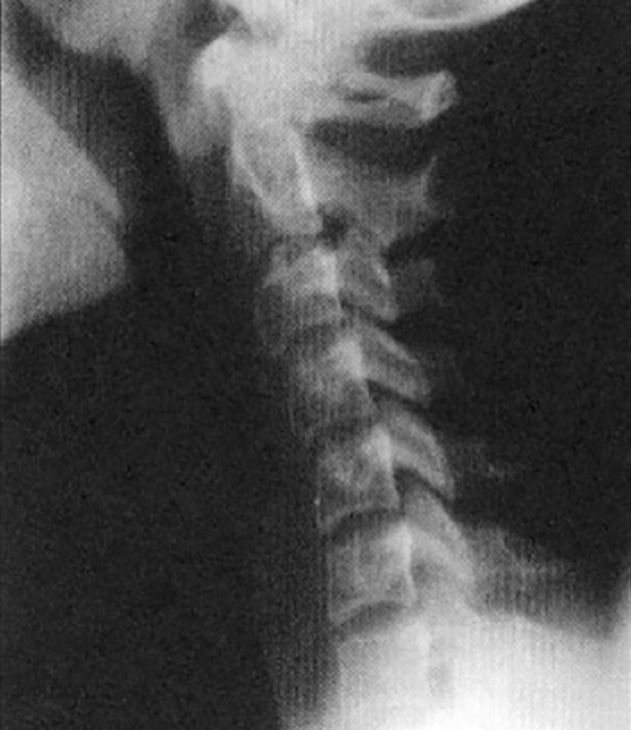

Normal Cervical Spine

Normal Curves and proper disc spacing allow normal function of the spine & nervous system.